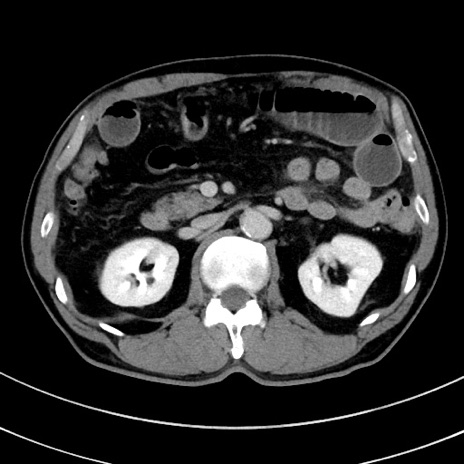

症例8(横断像)

【症例】 60歳代男性

【主訴】 黒色吐物

【現病歴】 4日前から嘔気自覚、2日前の朝食後にも嘔気あり、自分で手で嘔吐反射起こし嘔吐したところ血が混ざっていたため受診。

【既往歴】 5年前汎発性腹膜炎を伴う急性虫垂炎で手術、高血圧、前立腺肥大症、高脂血症

【身体所見】 腹部正中に手術癩痕あり 腹部平坦・軟圧痛なし膨満感あり

【データ】WBC 8400、CRP 4.54